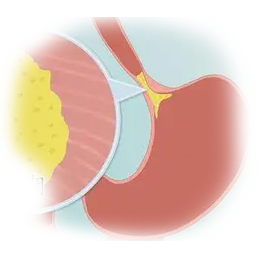

ξΎΟ≈Α© «ΖΔ…ζ‘ΎξΎΟ≈≤ΩΈΜΒΡΕώ–‘÷ΉΝωΘ§’β“Μ«χ”ρΈΜ”Ύ ≥Ιήœ¬ΕΥ”κΈΗΫΜΫγ¥ΠΘ§ «ΈΗ ≥ΙήΝ§Ϋ”ΒΡΙΐΕ…ΕΈΓΘ”…”ΎΤδΫβΤ ΈΜ÷ΟΧΊ βΘ§ξΎΟ≈Α©Φ»ΨΏ”– ≥ΙήΑ©ΒΡΡ≥–©ΧΊΒψΘ§“≤”κΈΗΑ©”–œύΥΤ÷°¥ΠΓΘΝΥΫβξΎΟ≈Α©ΒΡ≤Γ“ρΓΔ÷ΔΉ¥ΓΔ’οΕœΚΆ÷ΈΝΤΖΫΖ®Θ§”–÷ζ”ΎΧαΗΏ‘γΤΎΖΔœ÷ΚΆ÷ΈΝΤ–ßΙϊΓΘ